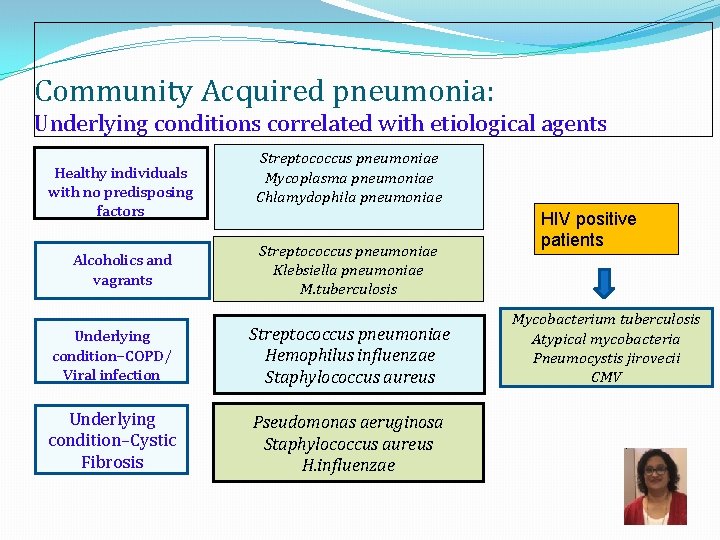

Community Acquired pneumonia: Underlying conditions correlated with etiological agents Healthy individuals with no predisposing factors Alcoholics and vagrants Streptococcus pneumoniae Mycoplasma pneumoniae Chlamydophila pneumoniae Streptococcus pneumoniae Klebsiella pneumoniae M. tuberculosis Underlying condition–COPD/ Viral infection Streptococcus pneumoniae Hemophilus influenzae Staphylococcus aureus Underlying condition–Cystic Fibrosis Pseudomonas aeruginosa Staphylococcus aureus H. influenzae HIV positive patients Mycobacterium tuberculosis Atypical mycobacteria Pneumocystis jirovecii CMV